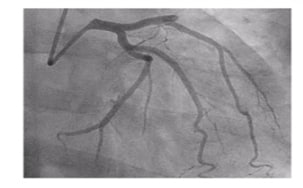

Critical violations ECG and coronary readings EChOKG changes

1 Acute coronary syndrome with

ST-segment elevation and coronary

syndrome without ST-segment elevation

2 Acute myocardial injury without vascular atherosclerosis